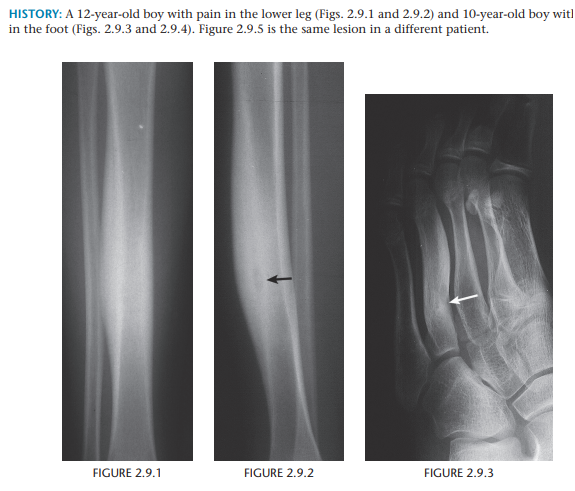

Osteoid Osteoma

Pain that is worse at night and relieved by salicylates is characteristic of osteoid osteoma.

Radiolucent nidus

Enhancing region on MRI